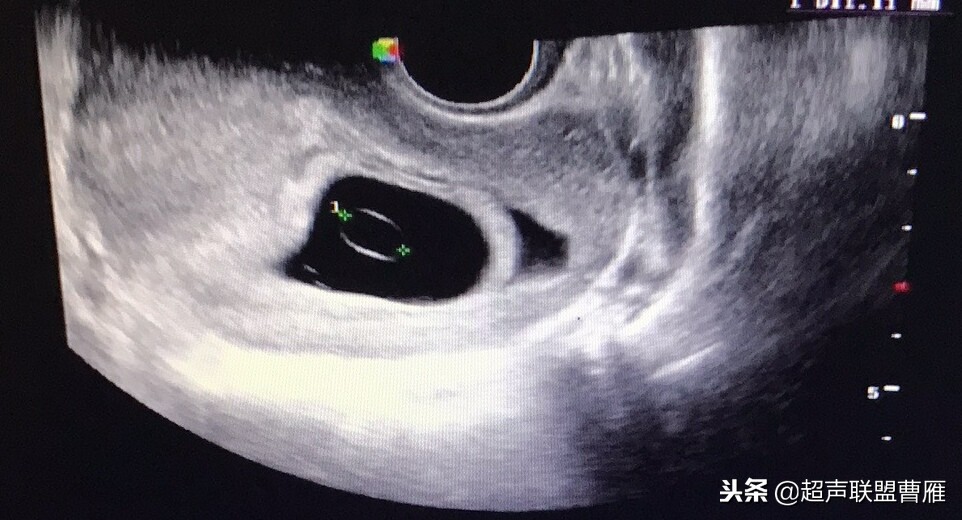

早孕 胚芽 卵黄囊

5周+ 、6周+ 声像图

孕7周左右(胚芽11mm 卵黄囊)

胎芽 卵黄囊 心管搏动信号

宫内早孕 (7周左右)